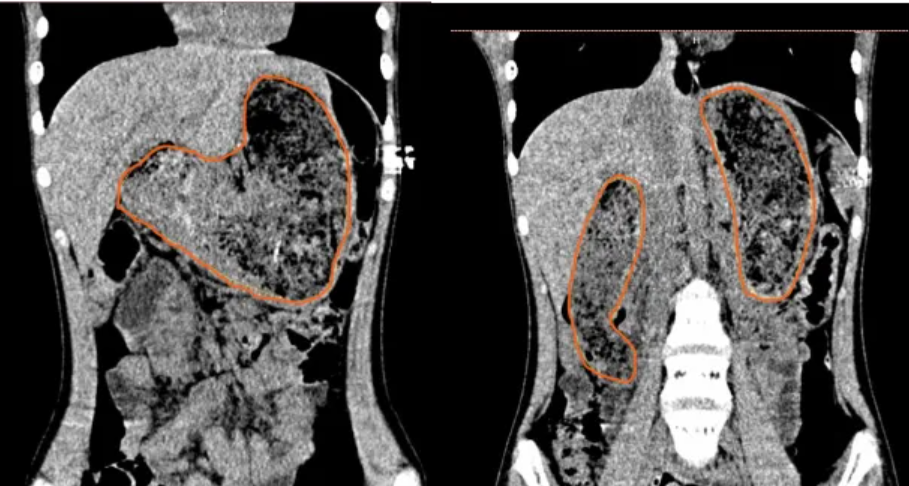

传统的剖腹胃切开取石手术虽能完整取出毛石,但手术创伤较大,对患儿的身体及心理可能产生不良影响。患儿术前CT检查发现毛石充满整个胃腔,且延伸至十二指肠降部,毛石形状不规则,呈横“Z”字形,大小约42厘米×7厘米×6.5厘米。为保证患儿身心健康,团队知难而进,选择了更为微创的腹腔镜手术方式。